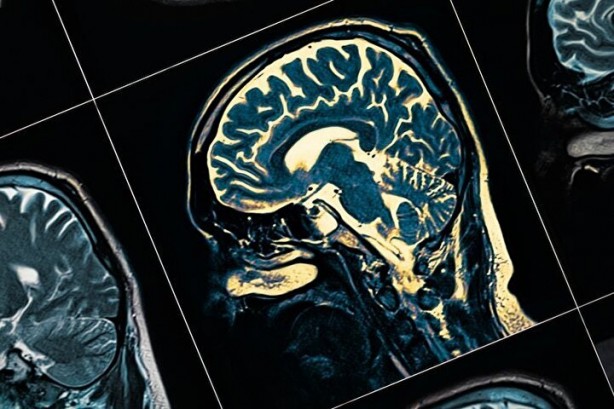

Milyonlarca kişi ihmal ediyor! Bu alışkanlıklar beyni çürütüyor

Beyin mucizevi bir organ ve tüm sağlığımızın da belirleyicisi. Bu nedenle onu korumak ve sağlığını güçlendirmek de büyük önem taşıyor. Muazzam boyutlarda bir depolama kapasitesine de sahip bu organ, tüm hayati işlevlerimizi de kontrol eder. Uzun ve sağlıklı bir yaşamın sırrı da, tam olarak bu yüzden beynimizden geçer. Ancak yaptığımız bazı hatalar doğrudan beynimize zarar verebilir. İster bilişsel performansınızı geliştirmek için öğleden sonra biraz uyumak, isterse demans riskinizi azaltmak için her gün dişlerinizi fırçalamak ve diş ipi kullanmak olsun, beyin açısından sağlıklı bir yaşam tarzı uygulamak günlük rutininizin bir parçası olmalıdır. Ve beyin sağlığınızı artırmak için yapabileceğiniz şeyler gibi, yaptığınız diğer bazı seçimler de beyninize zarar verebilir.